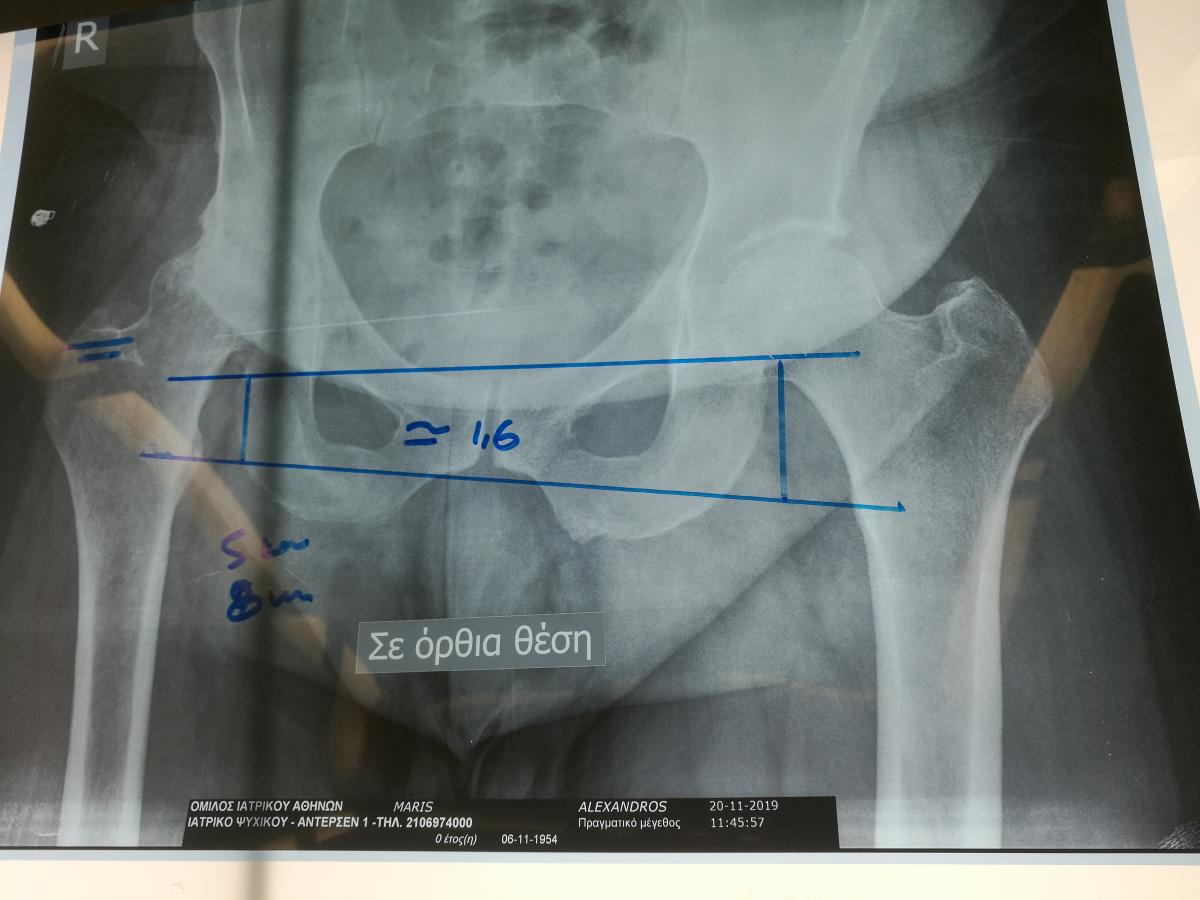

Компанія Lima надала стажування в ортопедичній приватній клініці місті Афіни Греція в листопаді 2019 року. Ендопротезування кульшового суглоба протезами компанії Lima малоінвазивним передньо-латеральний доступом у професора Христодулоса.